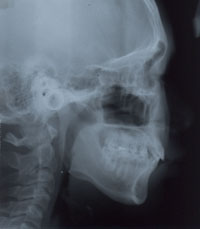

15세 7개월 된 남학생이 상악전치부 spacing을 주소로 내원하였다. 방사선사진을 촬영하고 상·하악 인상을 채득한 후 통상적인 방법으로 교정진단을 한 결과 다음과 같은 problem을 갖는 것으로 진단되었다 (그림 1,2).

그림 1. 15세 7개월 된 남학생의 내원시 구강내 모습으로 상악 좌우 측절치 결손으로 전치부 spacing을 나타내고 있다.

측모두부방사선규격사진에서는 상악골이 다소 돌출되어 있는 양상을 보이고 있는 것 외에는 두드러진 문제가 보이지 않았다. 파노라마 사진에서 상악중철치의 치근이 짧은 것이 눈에 띄었으며 좌우 견치가, 특히 좌측 견치가 견치위치라기보다는 측절치 위치에 자리잡은 것으로 나타났다. 석고모형 분석 결과 상악의 공간 양은 약 16mm로 측정되었으며 개개 치아크기를 평균치와 비교시 상악 양 중철치가 두드러지게 작은 것을 알 수 있었다. 반면 하악은 정상적인 배열을 보였다. 상·하악 교합 분석시 좌측은 정상적인 Cl I을 보였으나 하악 치열 정중선의 우측 편위와 함께 우측교합은 Cl II를 나타내었다. OB과 OJ은 3.0과 3.5mm로 정상보다 1.0 또는 1.5mm 큰 양상을 보였다 (그림 2,3).